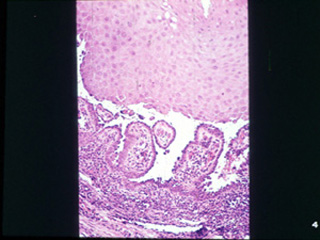

| Hay una apariencia característica histológica de la

enfermedad. Las vesículas son intraepiteliales generalmente suprabasal

. También hay una respuesta inflamatoria mixta en el tejido conjuntivo

| A mayor resolución se puede observar lo antes dicho;

las ampollas o vesículas son suprabasal. |

A una

mayor resolución las células de la capa de Malpighi sufren un doble

proceso, acantolítico (ruptura de los puentes intercelulares) y

degenerativo. |